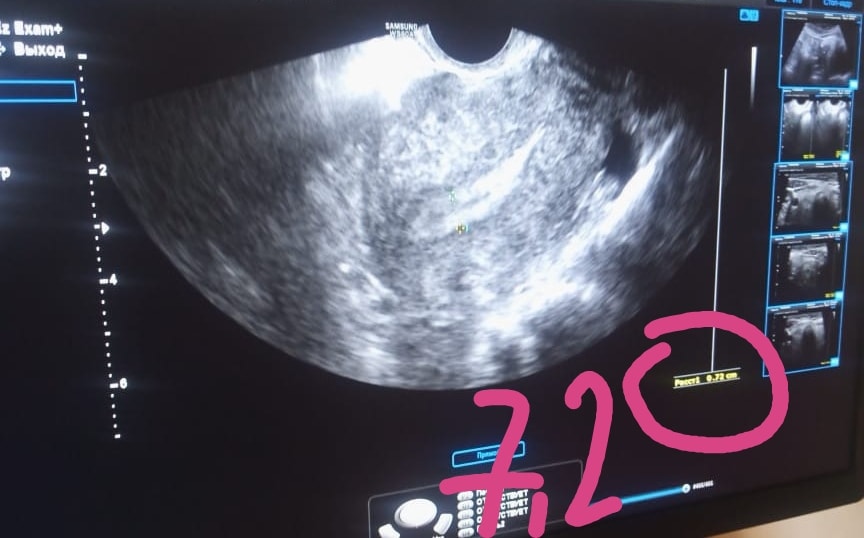

У меня до ввода утрожестан 11мм

Через 4 дня 6,8мм😭😭😭

Прогестерон на 2дпо 20нг